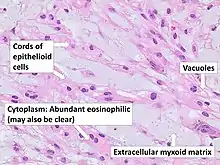

There are three histological variants of chordoma: conventional,[14] chondroid and dedifferentiated.

- The histological appearance of classical chordoma is of a lobulated tumor composed of groups of cells separated by fibrous septa. The cells have small round nuclei and abundant vacuolated cytoplasm, sometimes described as physaliferous (having bubbles or vacuoles).

- Chondroid chordomas histologically show features of both chordoma and chondrosarcoma.